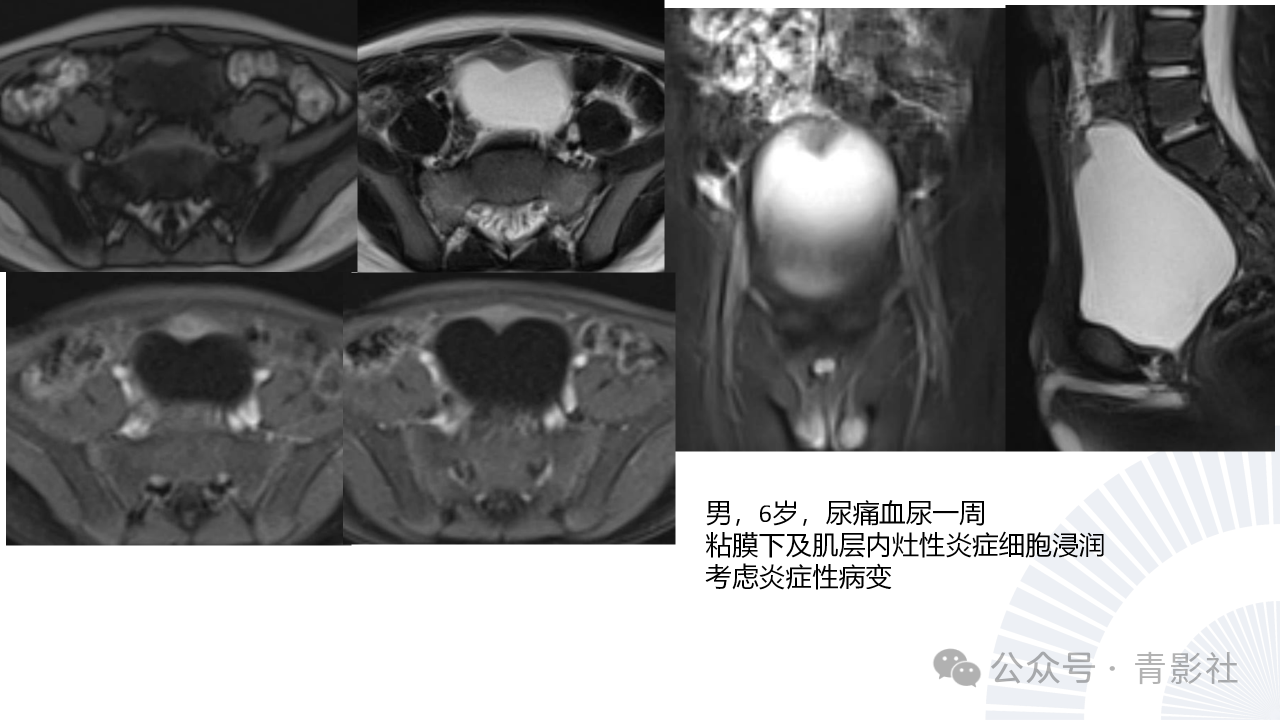

儿童膀胱肿瘤诊断要点及陷阱